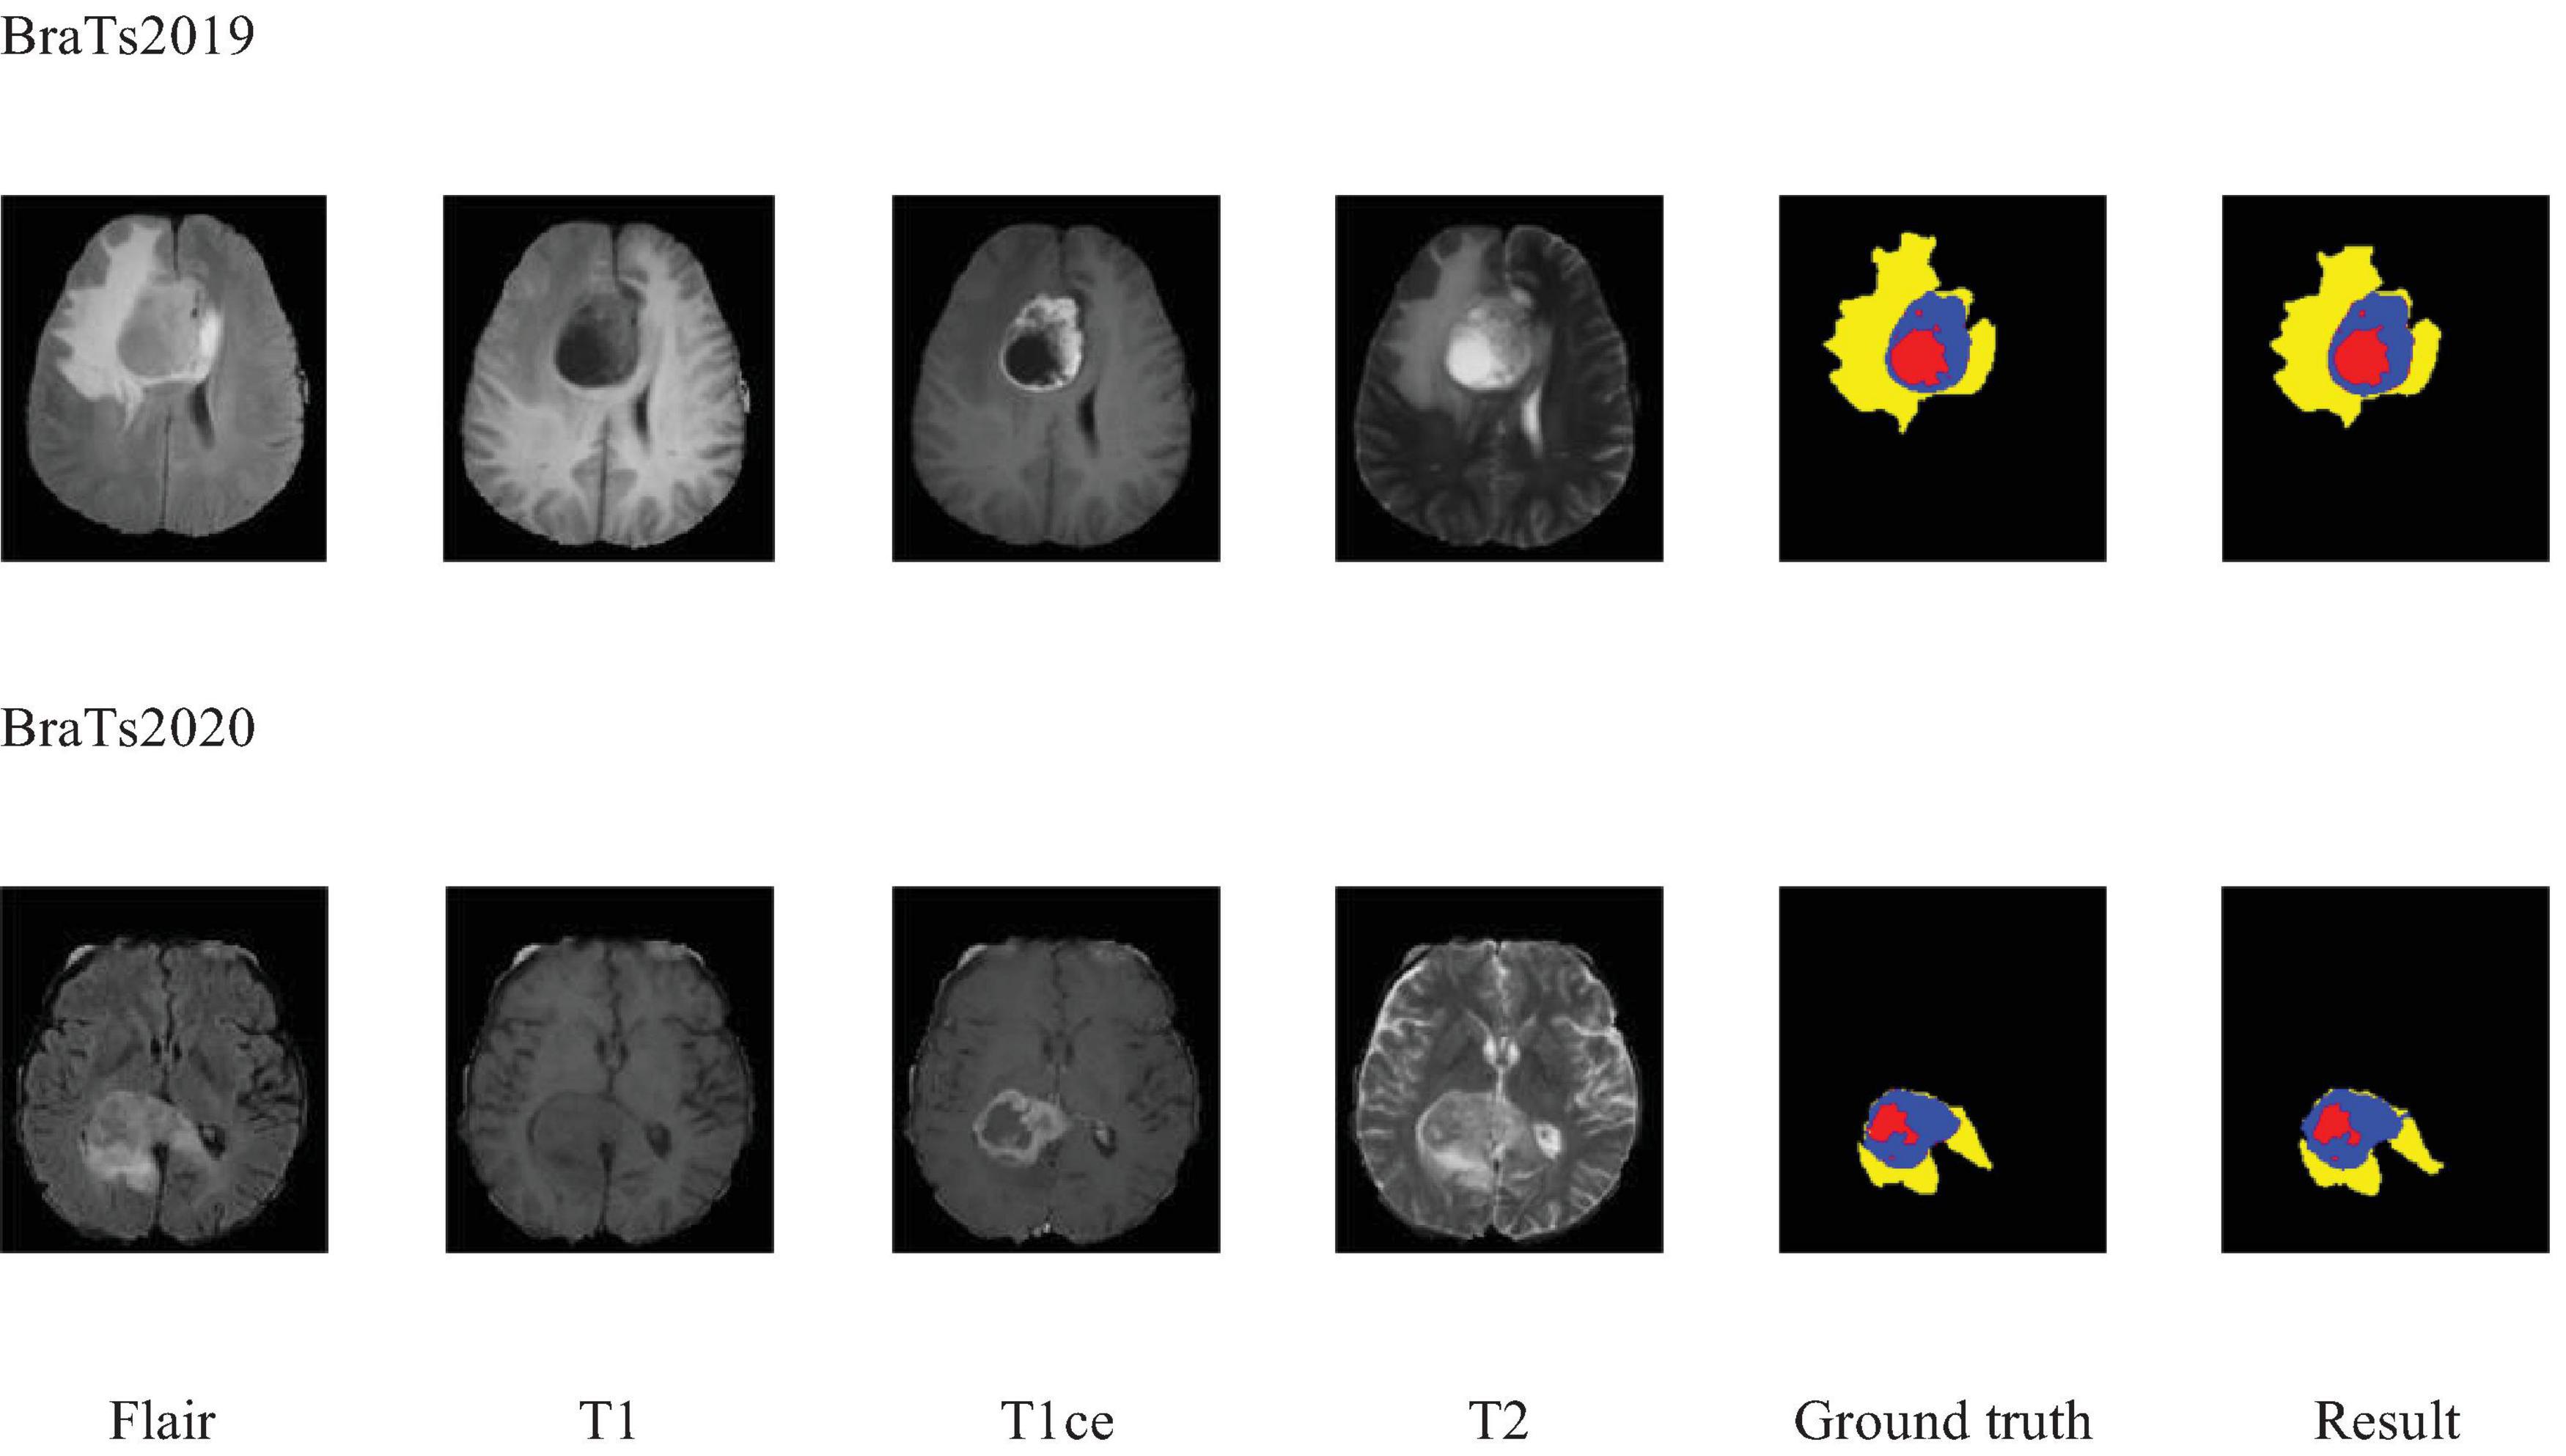

Additionally, to visually demonstrate the segmentation outcomes, we processed the model outputs for visualization. Figure 4 illustrates that the segmentation findings indicate MAUNet’s capability to precisely identify lesion sites, highlighting the model’s potential for clinical applications. To further illustrate the segmentation results and provide a visual representation of their distribution, box plots (Boxplot) were utilized. Figure 5 presents box plots summarizing the segmentation performance of MAUNet on the BraTS2019 and BraTS2020 brain-tumor segmentation datasets. The median Dice coefficient of every box plot lies approximately between 0.80 and 1.00, demonstrating that MAUNet achieves high segmentation accuracy across the three tumor sub-regions. The low height of each box indicates that most observations are concentrated at high Dice values, confirming the model’s stable performance. There are also some outliers in the figure, but they are few in number, indicating that the model shows slight fluctuations on individual samples. Overall, Figure 5 shows that MAUNet performs well in the task of brain tumor segmentation, with high accuracy and stability.

Figure 4. Visualization of the segmentation results of MAUNet. (Red, blue, and yellow indicate necrotic tumor core (NCR), enhanced tumor (ET), and peritumoral edema (ED), respectively).